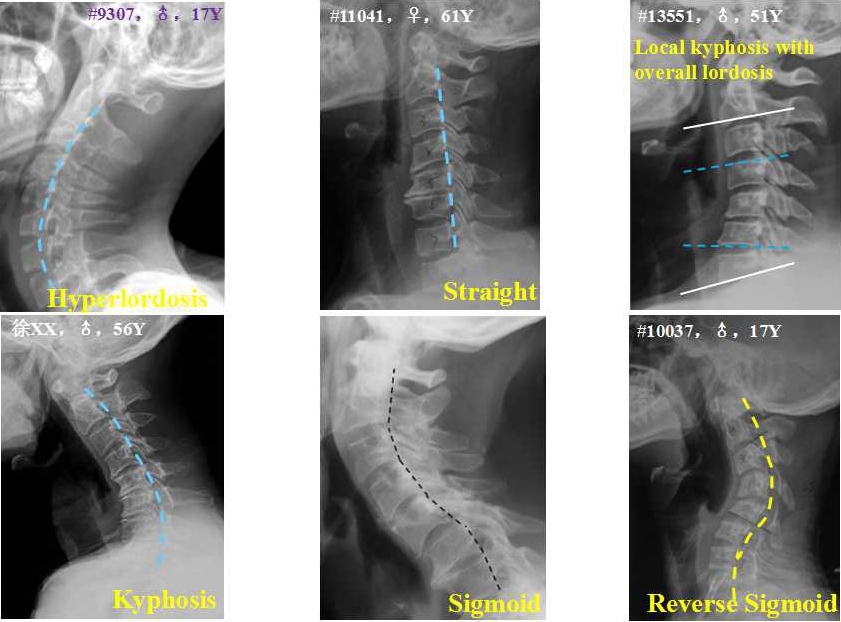

颈椎矢状面分型可包括:正常前凸型、过度前凸型、生理曲度变直型、后凸型、“S”型、反“S”型及整体前凸伴局部后凸型。退变性颈椎后凸合并椎管狭窄(Degenerative cervical kyphosis with stenosis,DCKS)指动力位平片上退变性颈椎疾病改变伴僵硬性颈椎后凸畸形,或MRI上显示颈椎管狭窄、颈脊髓压迫伴局部后凸畸形。(图1)

图1. 颈椎矢状面分型